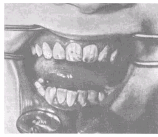

Различают несколько вариантов нормального П. (ортогнатический, прогенический, прямой, бипрогнатический). Они характеризуются смыканием зубных рядов на всем протяжении и отличаются друг от друга лишь особенностями смыкания функционально ориентированных групп зубов, в частности передних. Эталонным принято считать ортогнатический прикус (рис. 5, а), при котором верхний зубной ряд на всем протяжении перекрывает нижний, а во фронтальном участке верхние резцы перекрывают нижние не более чем на 1

/3

коронковой части зуба; между резцами верхней и нижней челюстей имеется режуще-бугорковый контакт. Прогенический прикус (рис. 5, б) отличается умеренным выстоянием нижнего зубного ряда. Прямой прикус (рис. 5, в) характеризуется тем, что верхние резцы не перекрывают нижние, а смыкаются режущими краями. При бипрогнатическом прикусе (рис. 5, г) верхние и нижние резцы наклонены в сторону преддверия рта, но между ними сохранен режуще-бугорковый контакт. Для всех вариантов нормального прикуса обязательным условием является нормальное функционирование зубочелюстной системы.

Патологический П. формируется при аномалиях зубов и челюстей врожденного или приобретенного характера (пародонтоз, пародонтит и др.). Основным отличием патологического прикуса от нормального является нарушение смыкания зубных рядов в различных направлениях вплоть до полного отсутствия на отдельных участках, что приводит к изменению функции зубочелюстной системы.

Существует множество классификаций аномалий П., однако общепринятой является международная классификация, предложенная в 1899 г. Энглом (Е.Н. Angle). В ее основе лежит соотношение первых моляров, что, по мнению Энгла, служит ключом окклюзии. В соответствии с классификацией к первому классу (рис. 6, а) относятся все аномалии, при которых первые моляры находятся в правильном соотношении (мезиально-шеечный бугор первого моляра верхней челюсти располагается в межбугорковой фиссуре первого моляра нижней челюсти), а все аномалии П. обусловлены изменениями зубов или челюстей спереди от первых моляров, например при скученности резцов, их протрузии (наклоне в сторону преддверия рта) или ретрузии (наклоне в сторону полости рта).

Во второй класс включены аномалии, при которых нарушено смыкание первых моляров и фронтальной группы зубов. Межбугорковая фиссура первого моляра нижней челюсти располагается позади мезиально-щечного бугра первого моляра верхней челюсти, т.е. нарушено смыкание зубов в сагиттальной плоскости (переднезаднем направлении). Подобные нарушения (так называемый дистальный прикус) могут быть обусловлены чрезмерным ростом верхней челюсти (прогнатией) или (реже) недоразвитием нижней челюсти (микрогенией). В зависимости от положения и смыкания фронтальной группы зубов во втором классе выделяют два подкласса: первый характеризуется протрузией резцов (рис. 6, б), второй — их ретрузией (рис. 6, в).

Третий класс (рис. 6, г) включает аномалии П., при которых межбугорковая фиссура первого моляра нижней челюсти располагается впереди мезиально-щечного бугра одноименного моляра верхней челюсти (мезиальный П., прогения, прогенический П., антериальный П.).

Кроме аномалий П. в сагиттальной плоскости существуют аномалии П. в вертикальной и трансверзальной плоскостях. К основным вертикальным аномалиям (определяются по отношению к горизонтальной плоскости) относится открытый и глубокий П. Открытый П. (рис. 7, а) — наличие щели между зубными рядами при их смыкании, чаще в области передних зубов, реже в области боковых. Иногда смыкаются только последние моляры, что приводит к выраженным нарушениям жевательной функции и особенно речи. При глубоком П. (рис. 7, б) передние зубы одной из челюстей в значительной степени перекрывают коронки зубов-антагонистов, нижние резцы не опираются на зубные бугорки верхних резцов, а соскальзывают к их десневому краю, что приводит к постоянному травмированию десен и неба; нижняя часть лица укорочена за счет уменьшения или дистального положения подбородка.

К трансверзальным аномалиям, определяемым по отношению к сагиттальной плоскости, относится перекрестный П. (рис. 7, в), при котором верхний зубной ряд в области боковых участков в значительной степени перекрывает нижний зубной ряд (латерогнатический П.) или нижний перекрывает верхний (латерогенический П.).